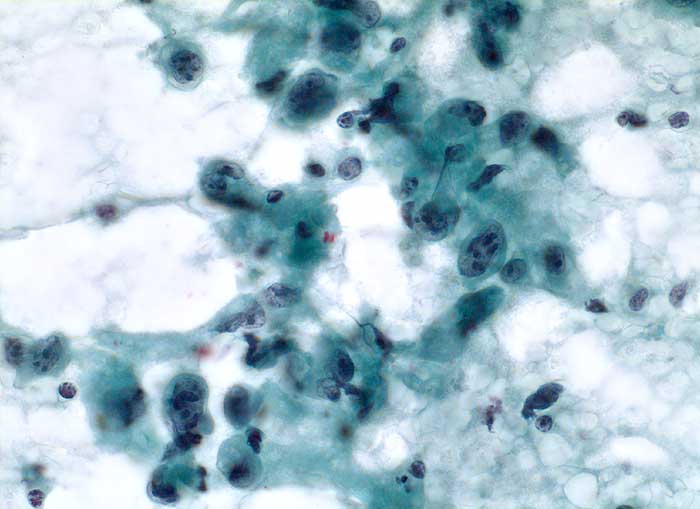

Feinnadelpunktion Schilddrüse: Der Ausstrich enthält atypische Zellen, welche wesentlich grösser sind als regelrechte Schilddrüsenepithelien. Die Tumorzellen sind ein oder mehrkernig. Die Kerne sind stark polymorph, grob strukturiert mit meist mehreren plumpen Nukleolen. Das Zytoplasma ist unterschiedlich breit.